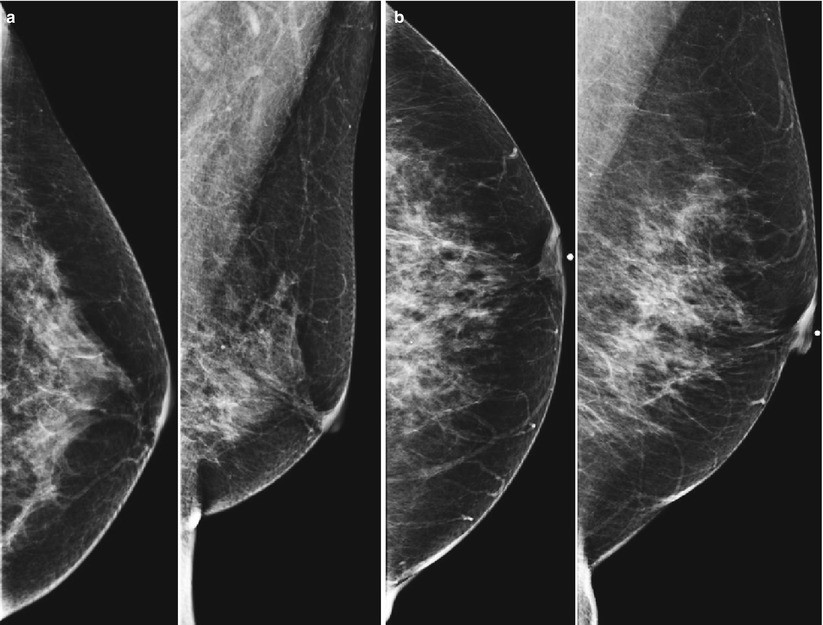

Chụp nhũ ảnh 2D là phương pháp truyền thống, chụp hình ảnh từ hai góc: thẳng và nghiêng. Mặc dù hình ảnh này giúp phát hiện các khối u hoặc bất thường trong mô vú, nhưng có thể bị giới hạn trong trường hợp mô vú dày hoặc chồng lớp.

Chụp nhũ ảnh 3D, hay còn gọi là Tomosynthesis, là công nghệ hiện đại giúp tạo ra hình ảnh 3 chiều từ nhiều góc độ khác nhau, hữu ích cho những người có mô vú dày hoặc yếu tố nguy cơ cao. Đặc biệt, máy chụp nhũ ảnh GE Senographe Pristina không chỉ cung cấp hình ảnh chi tiết mà còn có công nghệ giúp giảm liều lượng tia X, mang lại độ an toàn cao hơn cho bệnh nhân.

- Hình ảnh rõ ràng và chi tiết hơn: Khả năng tạo hình ảnh 3 chiều giúp bác sĩ quan sát rõ các chi tiết của mô vú, phát hiện các khối u nhỏ hơn, loại bỏ hiện tượng chồng lớp mô.

- Phù hợp cho người có mô vú dày: Hình ảnh 3D giúp làm rõ các bất thường trong trường hợp mô vú dày, giảm thiểu sự chồng lớp.